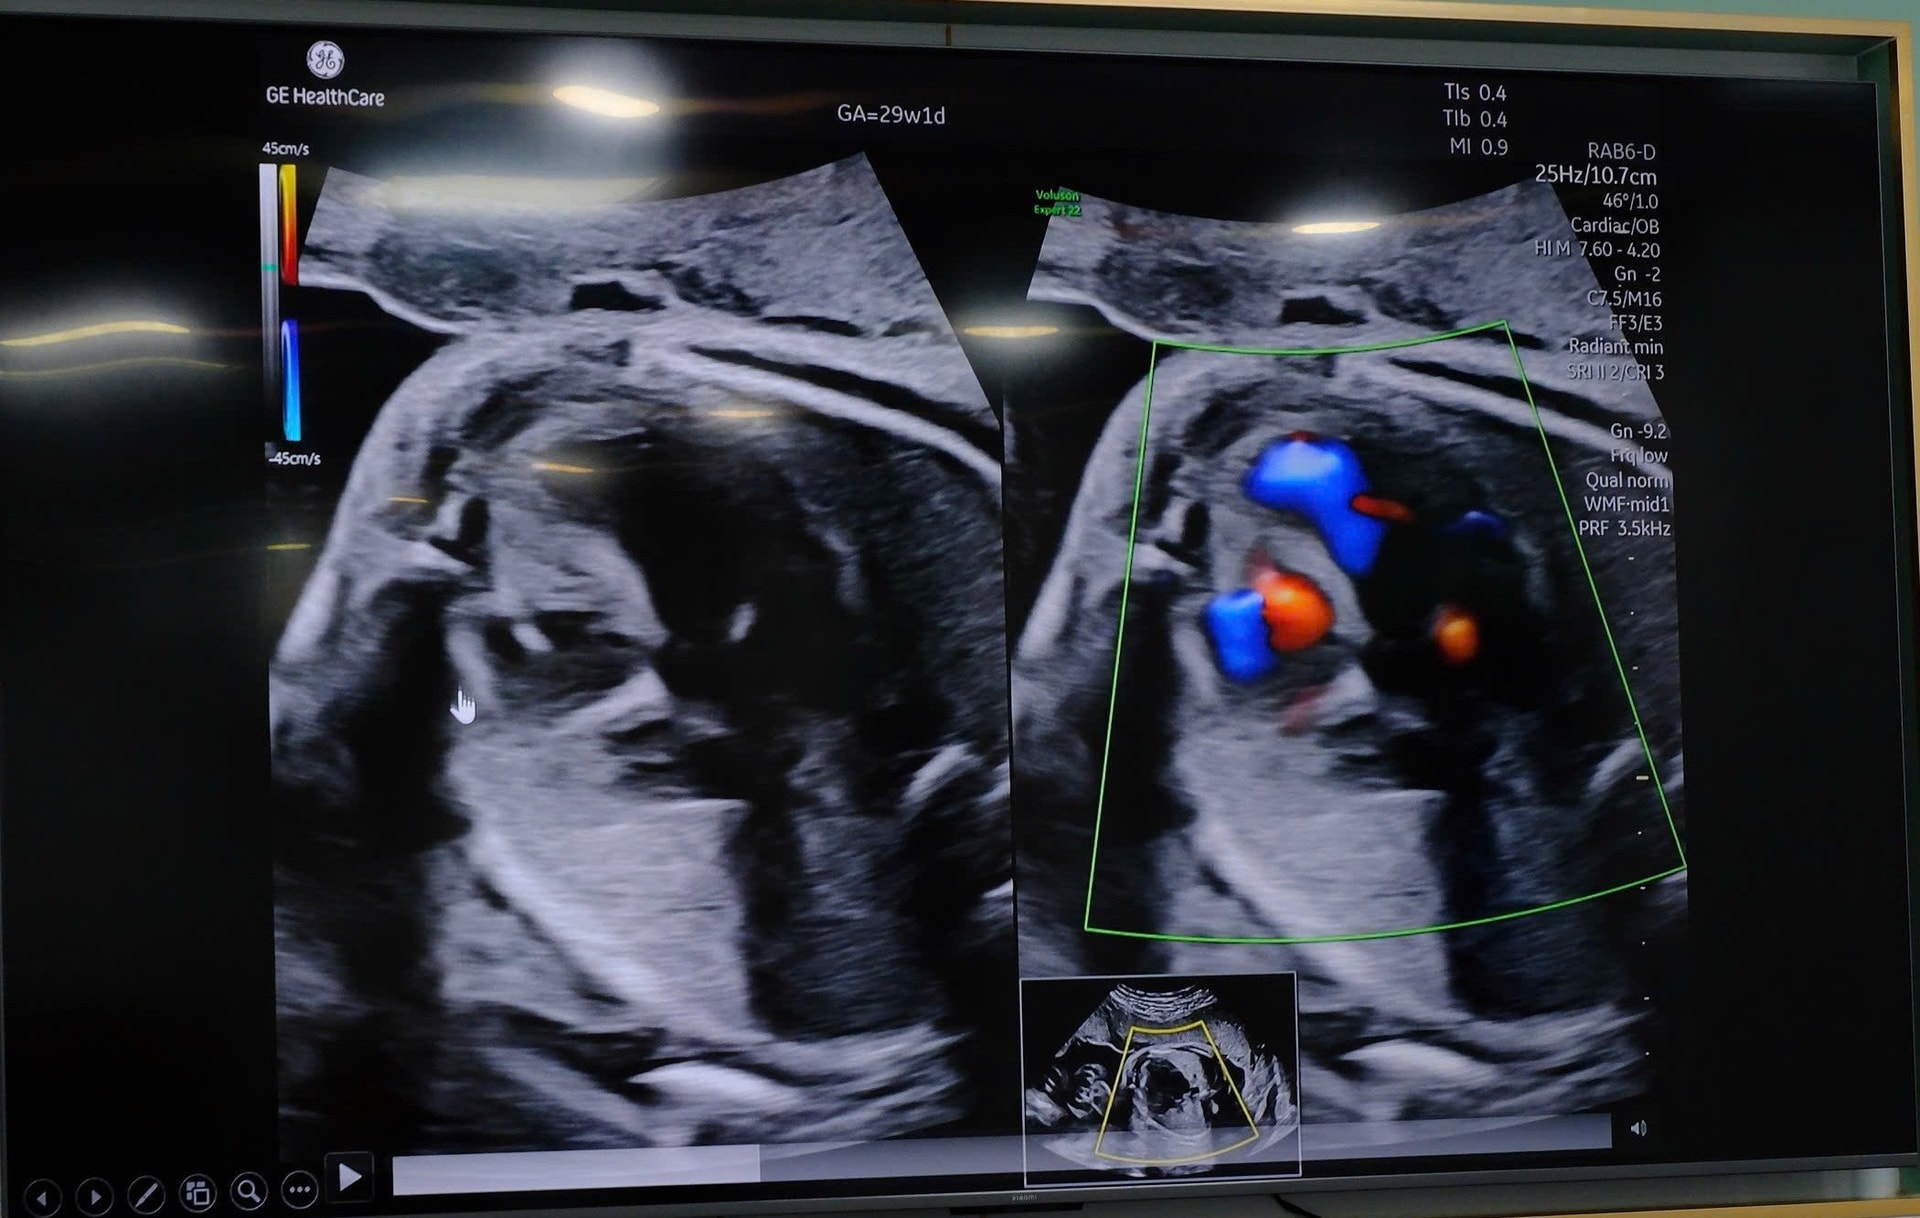

Hình ảnh học cho thấy sự bất thường của tim thai.

Trong quá trình theo dõi tiếp theo, bệnh lý tim thai có xu hướng tiến triển, với biểu hiện thiểu sản thất phải tăng dần cả về hình thái và chức năng, nguy cơ cao diễn tiến thành tim một thất nếu không can thiệp.

Sau khi tối ưu tư thế, quá trình xuyên kim qua thành bụng mẹ – tử cung – lồng ngực thai nhi và bơm bóng nong van động mạch phổi được thực hiện thuận lợi. Ca can thiệp thành công ngay lần xuyên kim đầu tiên, đảm bảo chính xác về kỹ thuật, hạn chế tối đa thời gian và nguy cơ cho cả mẹ và thai nhi.

Quá trình thực hiện can thiệp bào thai